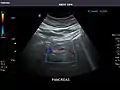

Aorta